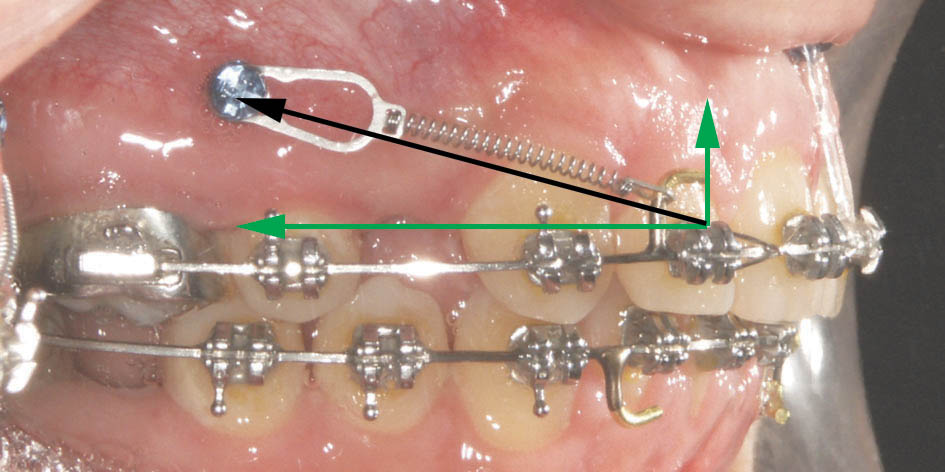

نیروی بستن فضا با مینی اسکرو مستقیم به سمت عقب نیست بلکه کمی به سمت لثه است (شکل 28-3). این نیرو به دو بردار تجزیه میشود: یکی افقی و دیگری عمودی. بردار افقی باعث بسته شدن فضای دندان کشیده شده میشود در حالی که بردار عمودی مانع دیپ بایت شدن بیمار میگردد.

در زمان بستن فضا با مینی اسکرو، دیگر خلفیها جلو نمیآیند و قدامیها هم که عقب میروند بردار نیرو به نحوی است که قدری اینترود میشوند بنابراین بایت بیمار بسته نمیشود. البته این بردار عمودی اینترود کننده فقط مانع بسته شدن بایت میگردد و اثری روی باز شدن بایت ندارد پس اگر بیمار دیپ بایت است و از مینی اسکرو استفاده میکنید باید قبل از بستن فضا بایت را حتماً باز کنید و به امید مینی اسکرو نباشید!